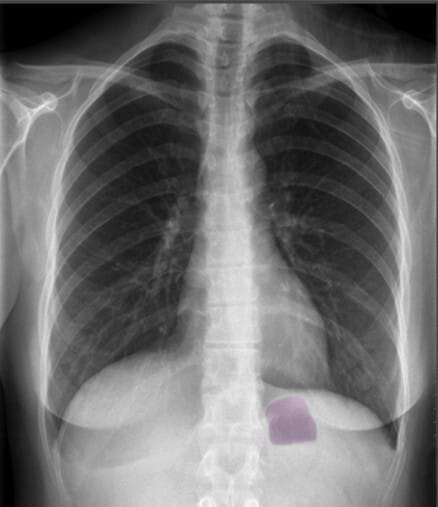

| 위 기포 (Gastric Bubble) |

| ✅ 좌측 횡격막 아래에서 나타나는 공기음영으로, 정상적인 해부학적 지표 중 하나입니다. 위치가 변하면 장폐색 등 복부 문제를 의심할 수 있습니다. |